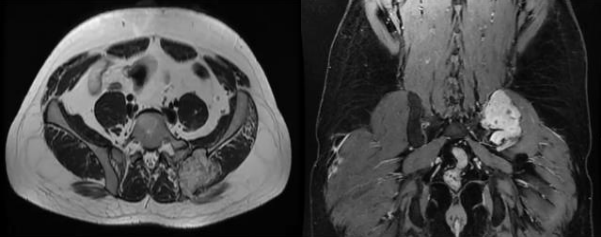

Figure 7,8,9,10, 11, 12

Case 3 - 35 year old male who presented with low back ache since 5 years and swelling since 2 year. Upon evaluation with X-ray of pelvis was found to have a lytic lesion in the left ileum on posterior aspect Fig-7. On MRI T2 hyper-intense lesion was found the posterior ileum with soft tissue component and cortical breech on posterior aspect measuring 5.7x 4.1x 7.3cm Fig-8.. Patient underwent extended curettage of the lesion and reconstruction with Poly-methyl methacrylate cement and Post-op Histopathology showed oval to spindle shaped cells with indistinct cell borders, round to oval hyperchromatic nucleus and moderate amount of cytoplasm- fibromatosis Fig-9. Upon follow up for 3 years patient is disease free.

Case 4- 21 year old female patient who presented with pain and swelling of the left lower back area since 8 months. Upon clinic radiological evaluation – on x ray was found to have a lytic lesion in the left postero-superior iliac wing and MRI showed T2 intermediate to hyper-intense lesion on the left iliac wing with cortical breech and extra-osseous soft tissue component involving the iliacus muscle anteriorly and gluteus medius posteriorly measuring 5.9x5.6x6.3 cm with T2 hypointense rim around the lesion Fig-10. Histopathology proved to be fibromatosis and after multidisciplinary team meeting patient was planned for extended curettage and reconstruction Fig-11. Reconstruction was done using poly-methyl methacrylate cement and two K-wire for stabilisation with post-op Histopathology confirming the diagnosis Fig-12. Upon one year of follow up patient does not have any complaints and doing well.